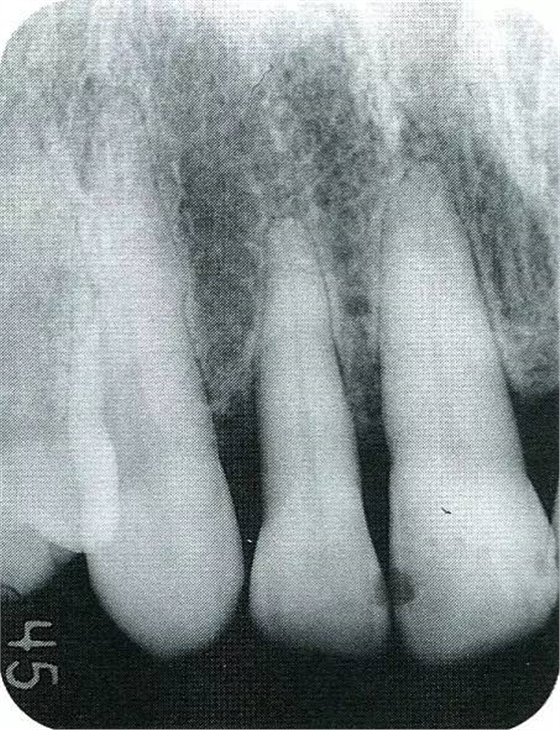

▲圖7-1左下6近中可觀察到3壁性垂直性骨缺損。此病例考慮到齦瓣供血關(guān)系,在前磨牙部位進(jìn)行了減張切開,沒有進(jìn)行縱切開。并利用刮治器、牙周外科用車針進(jìn)行了徹底的骨缺損部位搔刮。

▲圖7-2術(shù)前x片。確認(rèn)存在垂直性深骨缺損。